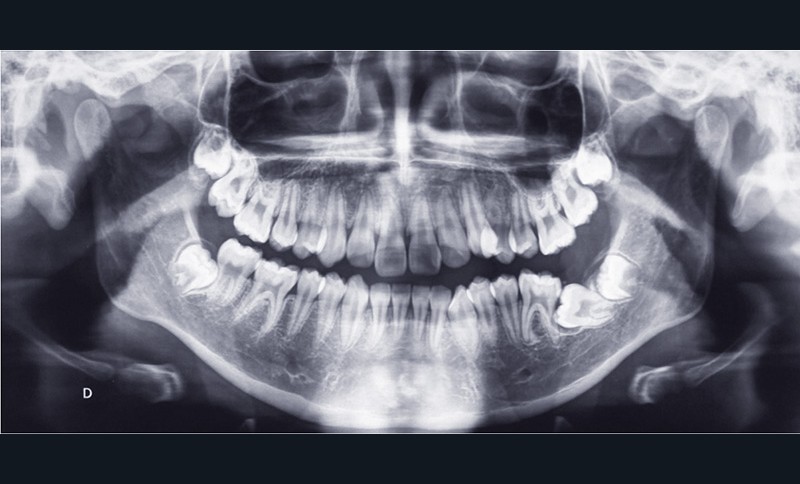

Le patient présente une DDM par encombrement antérieur et postérieur, des incisives mandibulaires vestibulo-versées et une 37 incluse en position horizontale (fig. 9).